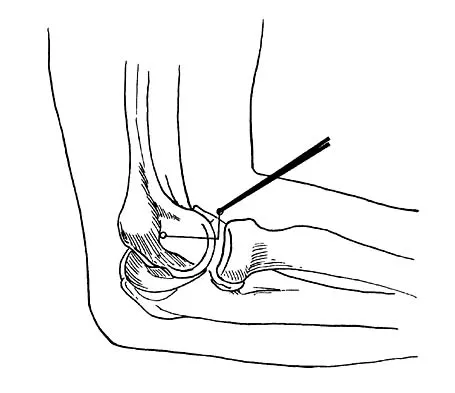

What nerve is at greatest risk of harm from the portal shown in Figure 36?

Explanation